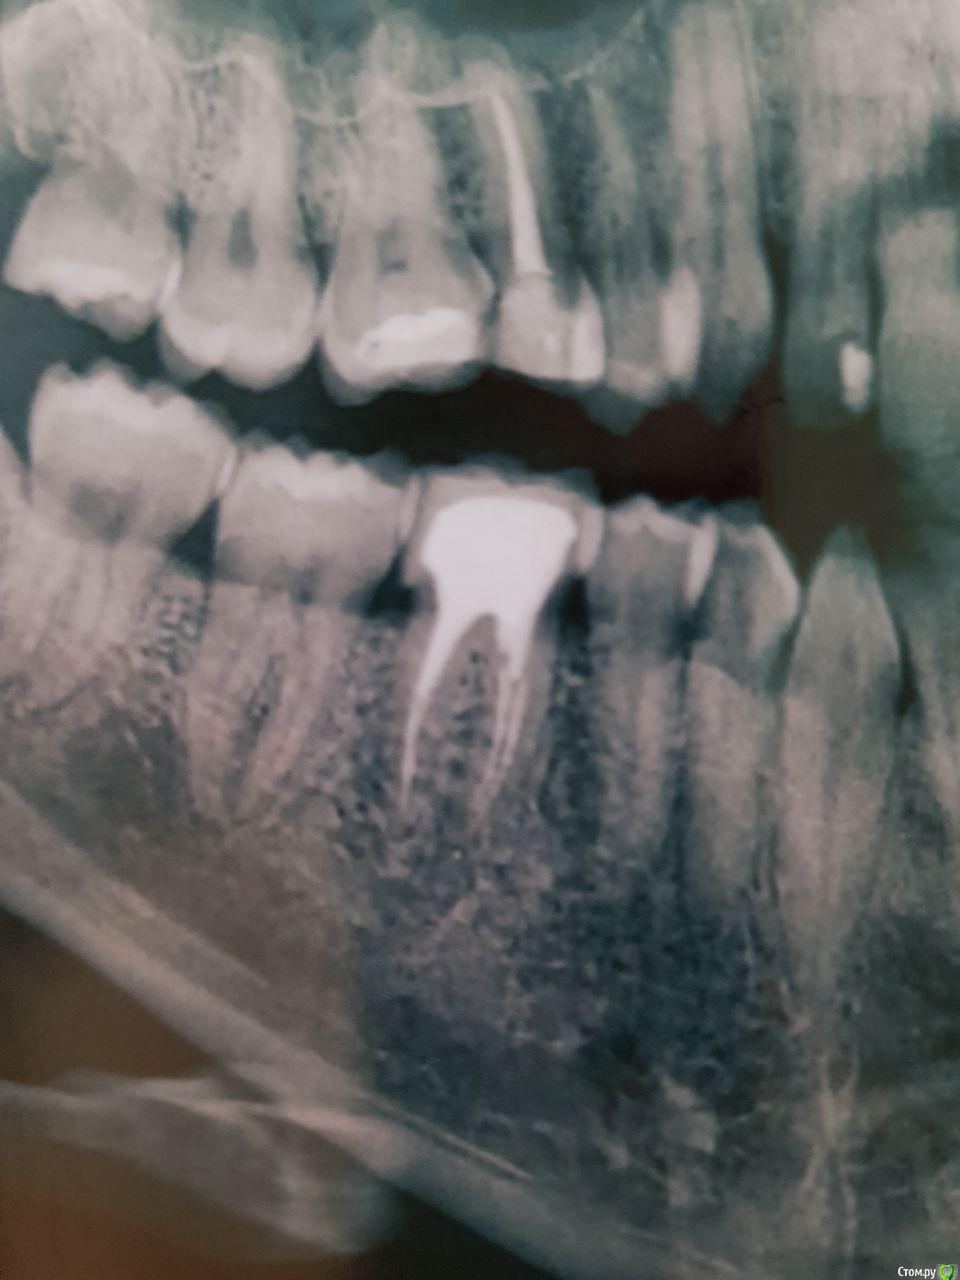

kungfucius Опубликовано 30 апреля, 2019 Поделиться Опубликовано 30 апреля, 2019 (изменено) Здравствуйте! Менее года назад ставил коронку на нижнюю шестерку. Где-то через полгода стало больно кусать что-либо твердое. Косточки от смородины или малины и кусочки черного перца вызывают боль. Иногда чувствую этот зуб от вибрации голоса когда говорю, иногда когда дотрагиваюсь до щеки. Стоматолог, который ставил коровку говорит, что он болеть не должен и с ним все нормально. Насколько хорошо запломбированы каналы (канал, который на снимке справа) и в чем еще может быть причина? Фото прилагаю: Изменено 30 апреля, 2019 пользователем kungfucius Ссылка на комментарий

red_butler Опубликовано 30 апреля, 2019 Поделиться Опубликовано 30 апреля, 2019 На пятом зубе нет коронки. Шестой нужно сделать прицельный снимок или Кт 1 Ссылка на комментарий